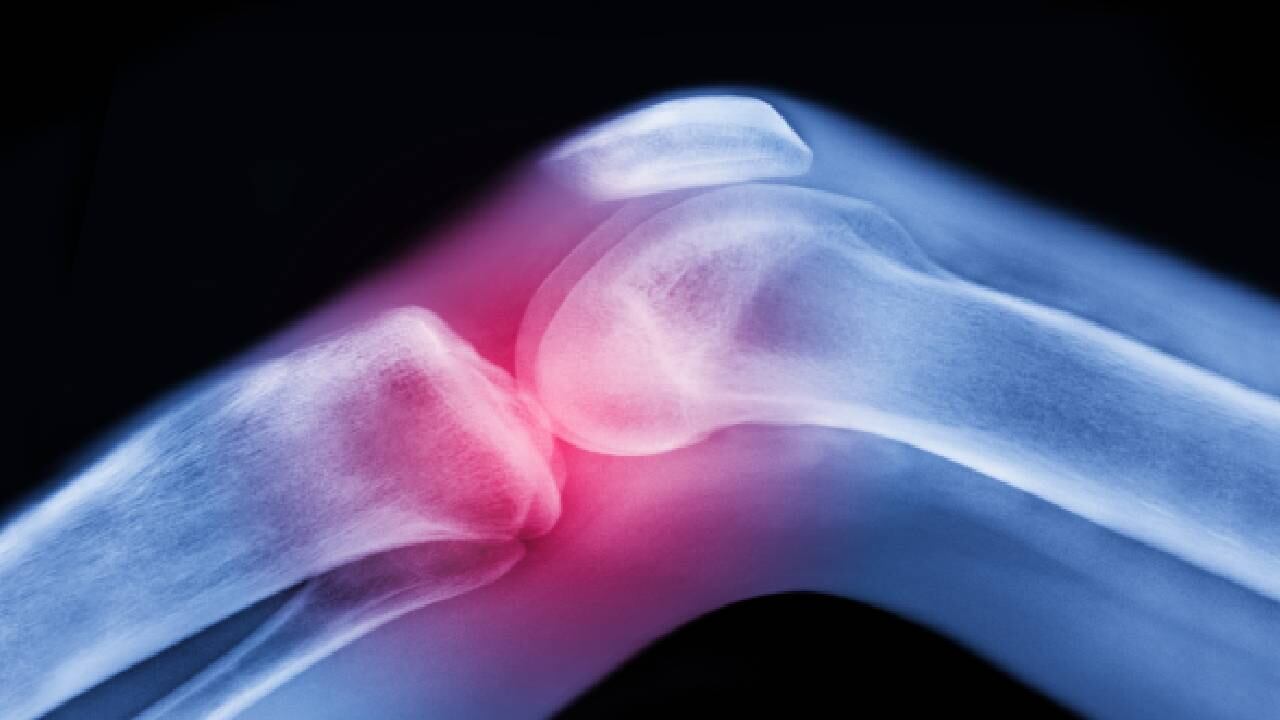

El dolor de rodilla puede empezar como una molestia leve y luego empeorar poco a poco. A menudo, se da después de una lesión o después de hacer ejercicio. Además, es un síntoma común en personas de todas las edades, de acuerdo con Medline Plus, la Biblioteca Nacional de Medicina de Estados Unidos.

Asimismo, Mayo Clinic, entidad sin ánimo de lucro dedicada a la práctica clínica, la educación y la investigación, explicó que la ubicación e intensidad del dolor de rodilla puede variar según la causa del problema y que los signos y síntomas que a veces acompañan el dolor de rodilla son inflamación y rigidez, enrojecimiento y temperatura al tacto, debilidad o inestabilidad, sonidos de chasquidos o crujidos e incapacidad de enderezar completamente la rodilla.